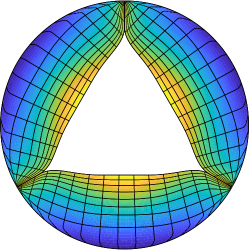

We constructed the model valves using a design-based approach to elasticity, which we introduced in our previous studies [16, 17]. With this method, we specified that the valve leaflets must, via tension in the leaflets, support a pressure. From this specification, we derived and solved a nonlinear partial differential equation for mechanical equilibrium of the leaflets under the prescribed load. By tuning free parameters and boundary conditions for these differential equations, we designed a closed configuration of the valve, including the tensions in the loaded configuration. From this closed configuration, we then derived the reference configuration and material properties of the model valve. This model was fiber based, in that the structure was discretized as a system of one-dimensional curves that fill a region in space. Alternatively, the model may be viewed as a system of nonlinear springs that includes a continuum limit. These methods were found to be highly effective under physiological pressures, opening and closing repeatedly over multiple cardiac cycles and achieving realistic flow rates with physiological driving pressures.

To design the model valve, we represented the leaflet as an unknown parametric surface

| (2) |

We assumed that the parameters conform to the fiber and cross fiber directions of the leaflets, meaning that for curves of constant on which varies represent the fibers, and curves of constant on which varies represent curves in the cross-fiber direction. Let single bars denote the Euclidean norm. We denoted the unit tangents to the surface as

| (3) |

which represented the local fiber and cross-fiber directions, respectively. These directions were not prescribed or required to be orthogonal. We denoted the magnitude of local membrane tensions in the circumferential and radial directions as and , respectively.

We then prescribed a uniform pressure load of mmHg, the approximate diastolic pressure load in the experimental data immediately following the closing transient. We then considered the mechanical equilibrium on an arbitrary patch of leaflet . This requirement gives the following integral balance of pressure and leaflet tensions:

| (4) | |||

Then, we applied the fundamental theorem of calculus to convert all single integrals to double integrals over the patch and swapped the order of integration formally as needed to obtain

| (5) |

This equation represents the integrated form of the equations of equilibrium. The patch is arbitrary, and so, formally assuming sufficient smoothness, the integrand must be zero. This gave the following partial differential equation form of the equations of equilibrium:

| (6) |

As written, this system of differential equations is not closed, as it has five unknowns, the three components of and the two tensions and only three equations, one for each component. To close the system, we temporarily specified that

| (7) |

This functional form allowed the solution of the differential equation to find heterogeneous tensions to support the prescribed pressure load, while preventing extreme local tensions from occurring. The parameters are tunable free parameters that we set to match the gross morphology of the prosthetic valve. The parameters represent the maximum allowable tension in the circumferential and radial directions. The parameters , which have units of cm, were tuned to control the gross morphology of the leaflets.

To tune these parameters and design a valve that corresponded to the prosthetic valve, we measured its gross morphology with a ruler and caliper. The free edge length of each leaflet was approximately 2.2 cm. We estimate the leaflet height at 1.3 cm, but this was highly dependent on loading; even pulling the leaflets flat along the ruler changed lengths substantially. The internal radius of leaflet attachment to the annulus was 1.0 cm and annular height was 1.1 cm. To match these values, we set the parameters to and dynes, respectively. The value of varied linearly from cm at the annulus to cm at the free edge. Taking a variable value of was necessary to avoid excessive billowing of the leaflet near the annulus while maintaining adequate free edge length. The value of was set to cm.

We discretized the system of equations (6) including the tension formulas (7) with centered finite differences. The position of the valve at the annulus and commissures was prescribed as a Dirichlet boundary condition. At the free edge, we prescribe zero-tension (homogeneous Neumann) boundary conditions. The resulting nonlinear system of equations was solved with Newton’s method with line search. Additionally, we applied the method of continuations on pressure, in which pressure is adaptively increased from an initial value of zero to the prescribed value of mmHg, and the solution with the previous pressure is used as the initial guess for Newton’s method with the subsequent pressure.

We then used the solution to equations (6), which represents the predicted loaded configuration of the valve, to derive a reference configuration and constitutive law. For each link in the discretized model, the solution included the loaded length and the tension needed to support the prescribed pressure load. Based on the experiments of Yap et al. [46], we prescribed uniform stretch ratios of circumferentially and = 1.54 radially, then used this information to compute the reference length for each link from its loaded length. For a link with length , we then solved for the rest length at the stretch corresponding to the direction of the link. We took the tension/stretch relationship to be exponential with a zero at , and based the shape, but not the local stiffness, on the strip biaxial tests of May-Newman et al. [29]. Based on a nonlinear least squares fit to their data, we took the exponential rate to be circumferentially and radially. For each link in the discretized, predicted loaded configuration with tension and the appropriate exponential rate and stretch for the circumferential or radial direction, we solved

| (8) |

for the local stiffness coefficient . Since the solution to equations (6) includes heterogeneous tensions, this resulted in heterogeneous material properties in the leaflets.

To generate an initial configuration suitable for FSI simulations, we sought a configuration of the leaflets that is open and free from external loading. Using the constitutive law we just set to determine tensions, we again solved the equilibrium equations (6) with mmHg. On the physical valve, a small portion of the leaflets point was attached radially inward from the commissures. To model this geometric feature, we force one eighth of the free edge points starting at each commissure of each leaflet to coincide (approximately 1/4 of each leaflet total), thus pinching the leaflets together. The remainder of the free edge was fixed as a Dirichlet boundary condition to ensure the leaflets do not self-intersect. This model has pre- or residual stretch and tension in this configuration, though substantially less than the predicted loaded configuration. Further, a configuration with zero tension, given the reference lengths that are computed locally for each link in the discretized model, may not exist.

Until this point, we used a membrane formulation of the leaflets. Next, we moved to a thickened formulation, while still using a fiber-based material model. To achieve a realistic thickness for the valve, we extruded the membrane for the valve normally in each direction, to form three adjacent membranes with a total thickness of mm, as reported in Sahasakul et al. [37]. This also served to mitigate the “grid aligned artifact” associated with large pressure differences across zero-thickness membranes in the IB method [16]. The stiffness of coefficients for each layer were set to be one third of the membrane stiffness coefficients computed previously. Linear springs of rest length mm were placed to keep the layers together through the simulation.

The gross morphology of the model valve that emerged from this process is shown in Figure 4. The free edge was 2.87 cm, corresponding to 3.3 cm in the predicted loaded configuration. After the pinching the leaflets together at the commissures, this left approximately 2.1 cm of free edge rest length per leaflet free to move independently of the other leaflets, within measurement error of ±0.1 cm from the free edge length of 2.2 cm measured on the prostheses. The leaflet rest height was 0.94 cm corresponding to a predicted loaded height of 1.44 cm. The measured leaflet height of 1.3 cm is nearly the predicted loaded height of 1.44 cm, which may be because the leaflets are so compliant in the radial direction, that pulling them flat to measure them achieved substantial stretches. The fiber orientation of the model runs from commissure to commissure and qualitatively matches experimental observations [38], though direct quantitative comparison is beyond the scope of this work. One minor limitation is that we do not add bending rigidity to the leaflets, beyond what emerges from the thickening process described above, and thus may not accurately capture leaflet flutter or other similar behaviors. Based on the thickness of mm, we estimated the mean tangent modulus at the predicted loaded stretches as dynes/cm2 circumferentially and dynes/cm2 radially. The prosthetic valve tissue is fixed in glutaraldehyde, and literature values for the fully-recruited circumferential tangent modulus of fixed porcine aortic valve tissue vary widely. Based on the experimental measurements of Billiar and Sacks and their constitutive law for valves fixed under 4 mmHg of pressure, we evaluated their constitutive law at the relevant stretches and and estimated the circumferential tangent modulus to be dynes/cm2 [6]. Rousseau et al. reported moduli ranging from to dynes/cm2, depending on the applied preload during fixation [36]. Sung et al. reported moduli ranging from to dynes/cm2, depending on fixation pressure [43]. Thus our estimated tangent modulus falls within the range of existing studies, so we considered our resultant modulus in good agreement given the complexity of the steps involved, phenomenological nature of the constitutive law and uncertainties in experiments. We do not have access to the precise material properties of the prosthetic valve, and further, the only literature we could find on the material properties of a similar prostheses reported the tangent modulus at one particular loading, which did not appear to be at a relevant stretch for comparisons with our model [19]. Thus, our model has material properties in a reasonable range for a fixed aortic valve prostheses (placed in the pulmonary position in our simulations), but it does not directly model the material properties of the prostheses.